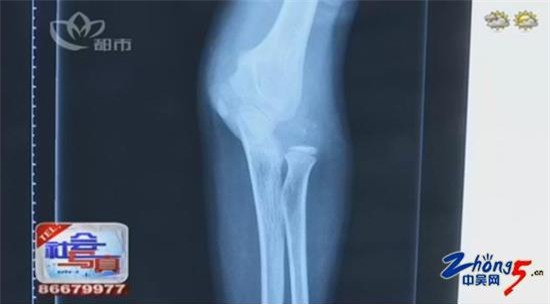

Hình chụp X-quang vị trí chấn thương của Viên Viên

Với kết quả bị gãy xương cánh tay phải và trật khớp khuỷu tay, Viên Viên được đưa vào phòng phẫu thuật chỉnh hình. Sau những nỗ lực của các bác sĩ, Viên Viên đã được phẫu thuật thành công và hiện đang trong giai đoạn hồi phục.